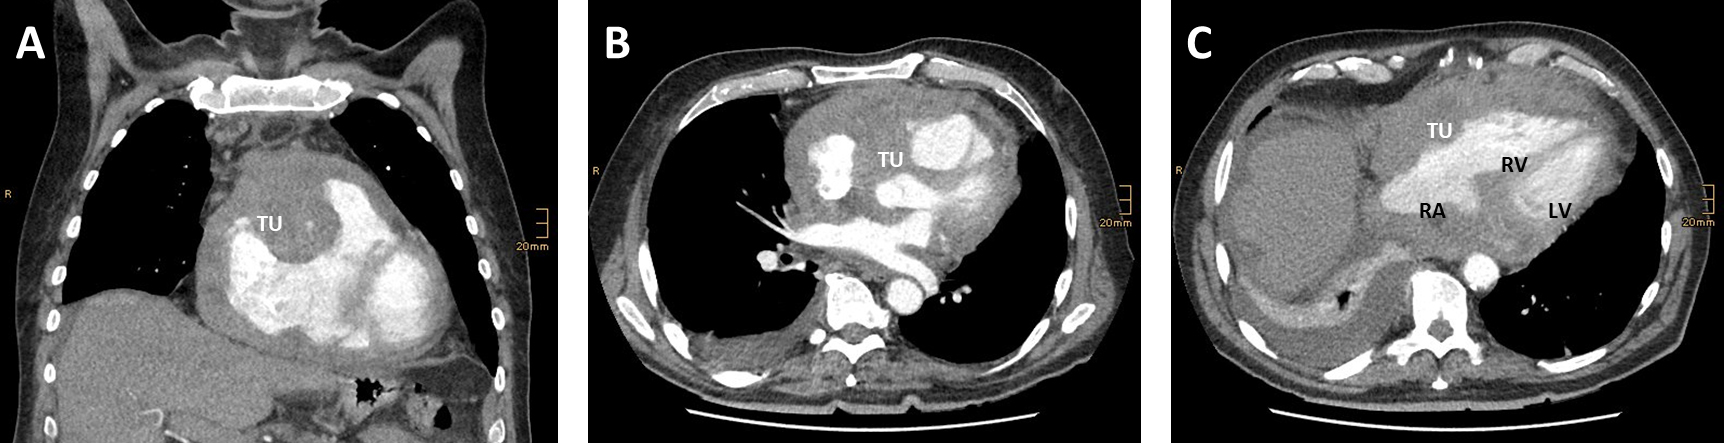

Etiologically, obstructive shock is caused by an impaired diastolic filling and thus a reduced cardiac RV- or LV-preload (venous return). A reduced preload is caused by tension pneumothorax, V. cava compression syndrome, mediastinal tumors, pericardial effusion or ventilation with a very high PEEP level. On the other hand, diseases which lead to an increased afterload and thus cardiac output may lead to obstructive shock. Causes associated with an increase in afterload are, for example, an aortic dissection, pulmonary embolism or Leriche syndrome. A pulmonary embolism or mediastinal space-occupying mass increases right-ventricular afterload, while decreasing left ventricular preload. The same mechanisms may occur in case of obstructive intracardial mass as displayed in Fig. 1, (Ref. [12]). Obstruction of the aortic blood flow however increases left ventricular afterload (e.g., Leriche syndrome [aortoiliac occlusive disease], aortic dissection) [13].

Fig. 1.Transversal (A,B) and coronal (C) reconstructions of a computed tomography (CT) angiography shwoeing a rare cause for obstructive shock. (A) Tumor mass (TU) infiltrating the right ventricular wall and left ventricular ouitflow tract. (B) The tumor (TU) mass compresses the right artrium (RA) and right ventricle (RV). The tumor has no direct contact to the left ventricle (LV). (C) Demonstrates tumor grophs along the right heart in coronal reconstruction. Adapted from [12].